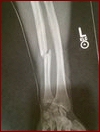

Something that we noticed was Pogue throwing more kicks and less and less punches as the rounds went on. He seemed to score often with his punch combinations in the early rounds but as the fight moved on, we saw less and less of his hands. On the other hand, we were surprised that we didn't see more "Explosive" power from the chiseled Hunt, especially after the opening round kick he threw in round 1. A kick that made even former IKF World Champion Mike LaBree happy he was retired. Oh and speaking of that kick, What kind of damage did it do? Well, here is where the overall picture of things becomes interesting. Keep in mind that within "Seconds" of round 1, Hunt landed a "Blistering" kick on Pogue's arm that we said was the loudest kick we had ever heard at ringside. After the event was over, Pogue found out that it's possible some of that noise came from.... A Bone Breaking! Now we're not just talking about a slight break, we're talking about a "BROKEN BONE!" How Broken you ask?

Feast your eyes on this X-Ray;

Looking back now it's amazing what Pogue accomplished in 12 rounds. With only "10 Days" notice Pogue went "12 Rounds" with a "7 Time World Champion" who was a full weightclass above his own fight weight. Not only that, Pogue battled for 12 rounds with only 1 arm... And coming from someone who is also a Professional Boxer, it makes you wonder a couple of things... 1, what could Randy have accomplished if he had say a month or two to prepare for this bout? 2, What could Randy have done if BOTH his arms were healthy throughout the bout... Oh, and there is a third thing... What could Randy have done against a contender in "His" own weightclass of Super Middleweight 165.1 lbs. - 172 lbs?